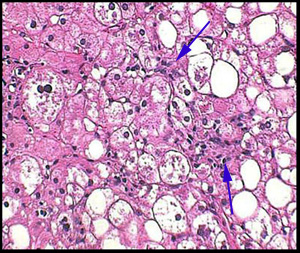

Até a década de 1980, acreditava-se que todo fígado com acúmulo de gordura e sinais de inflamação (hepatite) era causado pelo consumo de álcool. Hoje pode parecer surpreendente, mas esse tipo de alteração é tão comum em usuários de álcool que mesmo que o paciente negasse o consumo de bebidas alcoólicas ainda era considerado como se estivesse mentindo. Em 1980, Ludwig e colaboradores descreveram com o nome esteato hepatite não alcoólica – EHNA (nonalcoholoic steatohepatitis – NASH) uma síndrome caracterizada por mulheres obesas e diabéticas que negavam o uso de álcool, mas apresentavam alterações no fígado muito semelhantes a da hepatite alcoólica, com aumento do volume do fígado, alterações em exames laboratoriais e biópsias com macrovesículas de gordura (daí o nome esteatose, que vem de gordura) nos hepatócitos , necrose (morte celular) focal, inflamação e lesões chamadas de corpúsculos de Mallory (achados até então considerados característicos da hepatite alcoólica).

Contributed by Yoshihiro Ikura, M.D. (fonte)

No entanto os exames de imagem, especialmente a ultrassonografia, podem errar o diagnóstico. Doenças como a hemocromatose (onde há acúmulo de ferro no fígado) e glicogenoses (acúmulo de metabólitos de glicogênio) podem ser muito semelhantes à esteatose. Assim, considera-se que o melhor exame para o diagnóstico da esteatose é a biópsia hepática com análise histopatológica do material coletado. Além de confirmar a presença do acúmulo de gordura e diferenciar de outras doenças, permite avaliar se há hepatite e o quanto a doença está avançada em termos de fibrose.